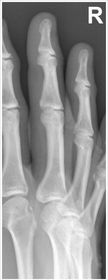

| Oblique Digit | finger not parallel to IR *should be more concave to one side* |

| Oblique Digit | finger not obliqued to 45 degrees - can't see the concavity of one side of the digit joint spaces closed |

| Lateral Digit | finger bent back - not truly lateral |

| Lateral Digit | artifact |

| What's the evaluation criteria for the PA Finger X-Ray? | ANATOMY: distal phalynx -> distal 1/2 of metacarpal demonstrated CRITERIA: - equal concavity on both sides of phalanges - IP and MCP open - no overlapping of adjacent fingers POSITIONING: CR perpendicular @ PIP joint |

| What's the evaluation criteria for the Lateral finger x-ray? | ANATOMY: entire digit demonstrated CRITERIA: open joint spaces concave to one side, while the dorsal side is straight no overlapping of adjacent fingers/soft tissues POSITIONING: CR perpendicular @ PIP joint |

| Oblique finger x-ray image criteria? | ANATOMY: entire digit demonstrated CRITERIA: more concavity to one side open joint spaces no superimposition of adjacent fingers POSITIONING: CR perpendicular @ PIP joint |